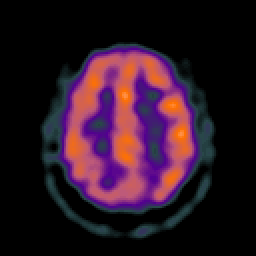

Glioma overlay -- Slice #21

[Home][Help][Clinical] Slice 21